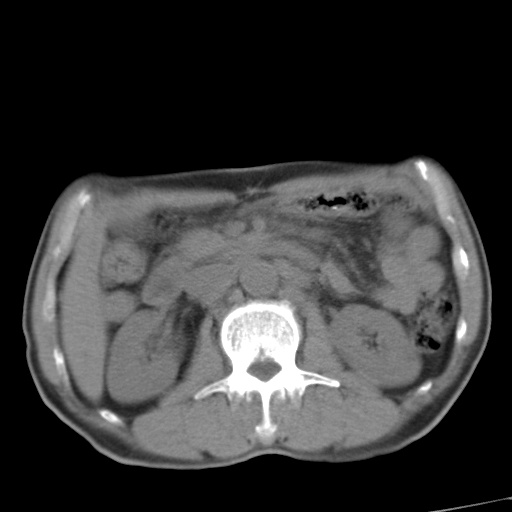

标题: CT17975:请求会诊。男、57岁。上腹部胀痛2天。临床诊断:糜 [打印本页]

标题: CT17975:请求会诊。男、57岁。上腹部胀痛2天。临床诊断:糜

肝脏多发类圆形低密度影,考虑肝脏转移瘤,肝胃韧带一淋巴结肿大,原发?胃癌?

考虑胃癌并肝脏及腹膜后淋巴结转移;不排除淋巴瘤。

肝内转移瘤,腹腔及腹膜后淋巴结转移。